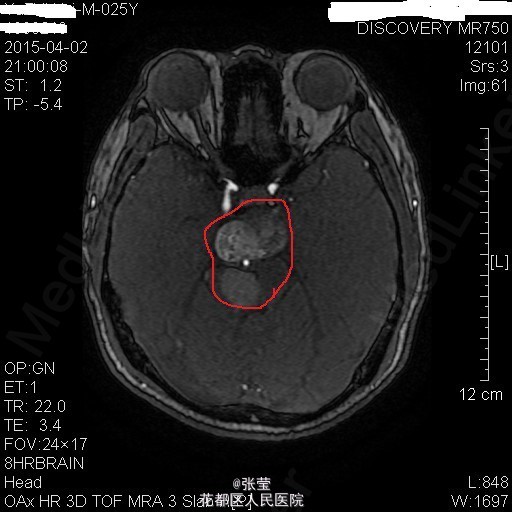

青年男性,主诉:头晕伴肢体乏力1周。 现病史:患者1周前始无明显诱因反复出现头晕,伴左侧肢体乏力、行走不稳,偶伴头痛、恶心感,休息后可稍缓解,无呕吐,无天旋地转感,无晕厥,无伴听力、记忆力减退等,发作无明显规律。至当地医院就诊,头部MR结果示:右间脑下方-脑干-桥前池-左鞍底区肿瘤,并瘤内卒中。

查体:神清,对答切题,双瞳等大等圆,直径约3mm,对光反射灵敏,双侧听力粗测正常,四肢肌力Ⅴ级。生理反射存在,病理征未引出。 辅查:颅脑MR:1、斜坡区占位,侵及中脑、脑桥右份及蝶窦,病灶ADC值增高,FA值下降,考虑脊索瘤并囊变、出血可能大。 2、MRA示双侧颈内动脉向外侧移位,余脑动脉未见明确异常。